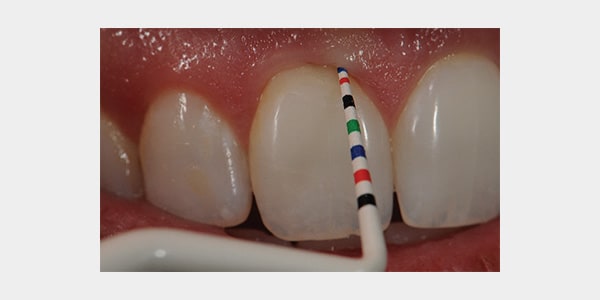

Hu-Friedy's Colorvue® Line of Probes feature a distinct color-coding design, offering a reliable and efficient solution to evaluate a patient's periodontal status. Offering high contrast and varied color millimeter markings, it takes the strain out of the clinician's eyes offering better visibility in intra-oral structures. Colorvue® line's rounded resin tips provide the optimal level of flexibility which ensures a more comfortable patient experience. Colorvue® tips are ideal for the delicate implant attachments as well. As an extra plus, the tips provide greater value to the office as they can be replaced, and each tip can be sterilized and used up to 30 times!

• Colorvue probes provide a fast and accurate evaluation of pocket depth and recession

• Tips are marked with vivid yellow and black color codes, enhancing contrast to intraoral structures